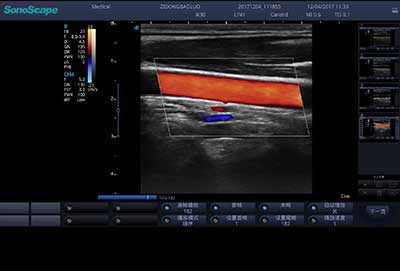

频谱自动包络